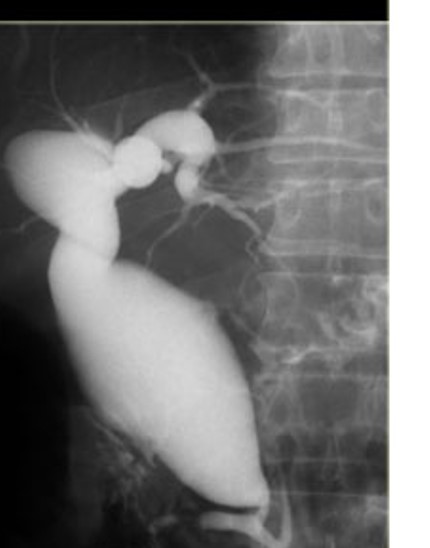

todani type III = choledococele at the intraduodenal bile duct

“cobra head”

todani type iii